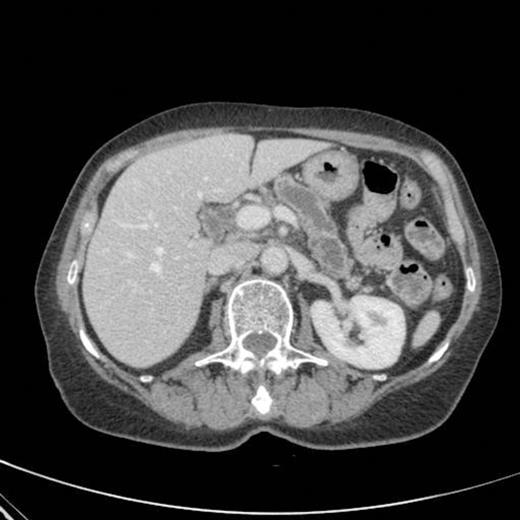

CT scan done at 10 years after initial diagnosis as part of routine surveillance revealed gross dilatation of main pancreatic duct to 10 mm along with a widely patent communication between the pancreatic duct and the stomach raising the possibility of a spontaneous gastro-pancreatic fistula measuring up to 19 mm associated with layering of mucin within the stomach. (Fig 3). The pancreas did not reveal any mass lesion and was globally atrophic. An upper GI endsocopy was done and this revealed a little crater with mucus plug in the body of the stomach along the lesser curve representing the opening of the gastropancreatic fistula. Biopsies taken around the fistula revealed non-specific inflammation. On clinic review, the patient complained of increased frequency of bowel habits, which was thought to be due to intestinal hurry caused by the fistula. This responded well to increased dose of creon.